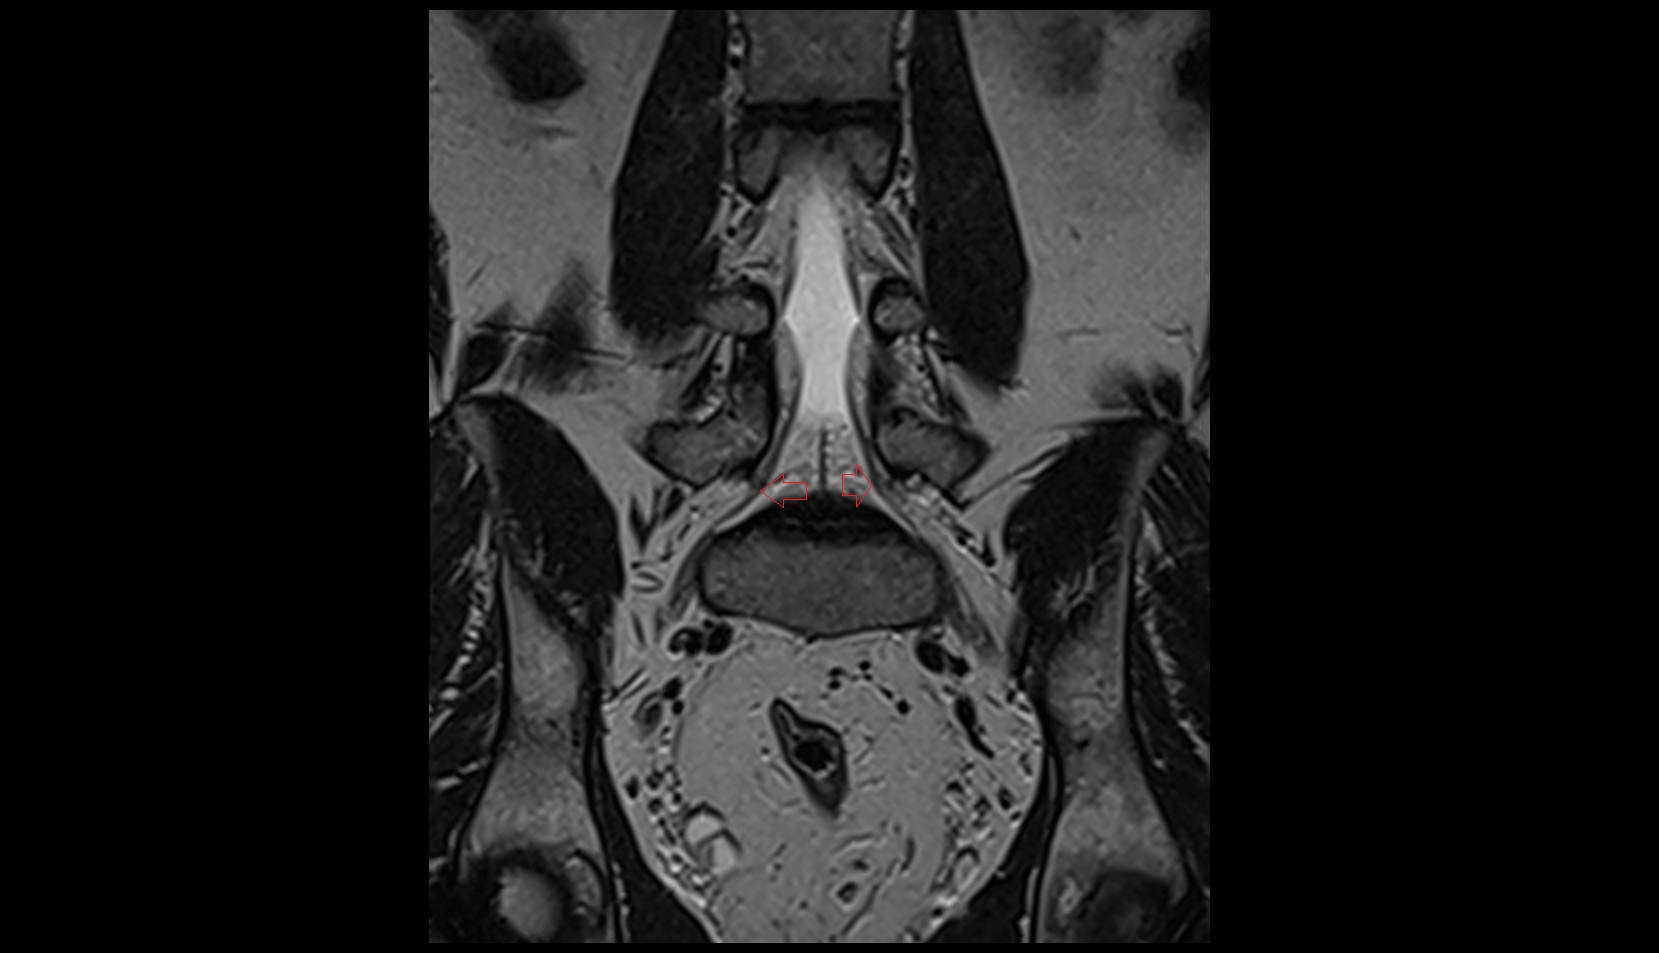

- Traversing nerve root of spinal nerve

- Exiting nerve root of spinal nerve

- Dorsal traversing nerve root

- Ventral traversing nerve root

- Dorsal exiting nerve root

- Ventral exiting nerve root

- Dorsal root ganglion of spinal nerve